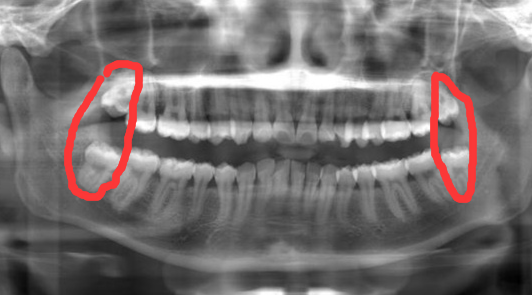

都会免费的为你拍片,检查你的牙齿情况。先是面诊,然后拍全景照,最后去做口腔扫描。不做检查不知道,一做才知道好好的牙齿为什么歪了。因为我那没有感觉的智齿诞生的时候把它挤歪了,自己却没当回事。好在智齿长得正。我的上牙正常萌出了,下牙位置正了,但是没有长出来,在肉里面,大概是不会再长了,但是有可能发炎。医生说我是牙性的(骨性是需要动手术的,风险很大),所以拔掉上面的两颗智齿,就可以腾出位置把牙齿内收。下牙拥挤的只需要简单的做下片切就可以排齐。消息还是好的,就直接缴费,确定整牙了。(下图圈起来的是智齿)